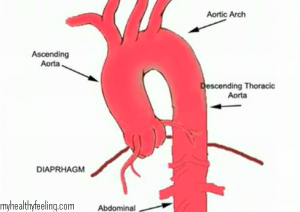

Marfan Syndrome is caused by a genetic defect. The gene that is impaired is FBN1 which has a connective protein called Fibrillin-1, it plays a crucial role in building the elastic tissue in the body. The genetic defect leads to overgrowth of bones, making them stretch long. This lead to tall height, limbs and arms. Also affected from Marfan Syndrome are the lung tissue, the eyes leading to cataract and other eye problems, the spinal cord tissue, the aorta, the main artery that circulates blood from the heart to various parts of the body. In fact, the syndrome can cause the aorta to stretch and weaken leading to aortic dilation or aortic aneurysm.

2. Echocardiogram, advisable to done every year to find out the basal position of the aorta

1. Medication to slow down the heart-rate. A cardiologist can address the problem of aorta and heart valves. He or she may give medication to reduce the quick heart rate that can put stress on the aorta. Beta blockers are given to slow the heart rate and reduce aortic dilation.Blood pressure can be reduced without further reducing heart rate than needed by ACE inhibitors and angiotensin II receptor antagonists

5. Pregnant women who have Marfan Syndome should be monitored minutely because there can be an increased pressure of the aorta and heart.

Marfan Syndome Life Expectancy

Most people who have Marfan Syndome die due to heart related complications. With good care and health, most people can still live beyond 60 years of age and even more. The complications associated with the disease include aortic rupture, dissecting aortic aneurysm, aortic regurgitation, heart failure, mitral valve prolapsed, vision related issues, bacterial endocarditiis and scoliosis etc.